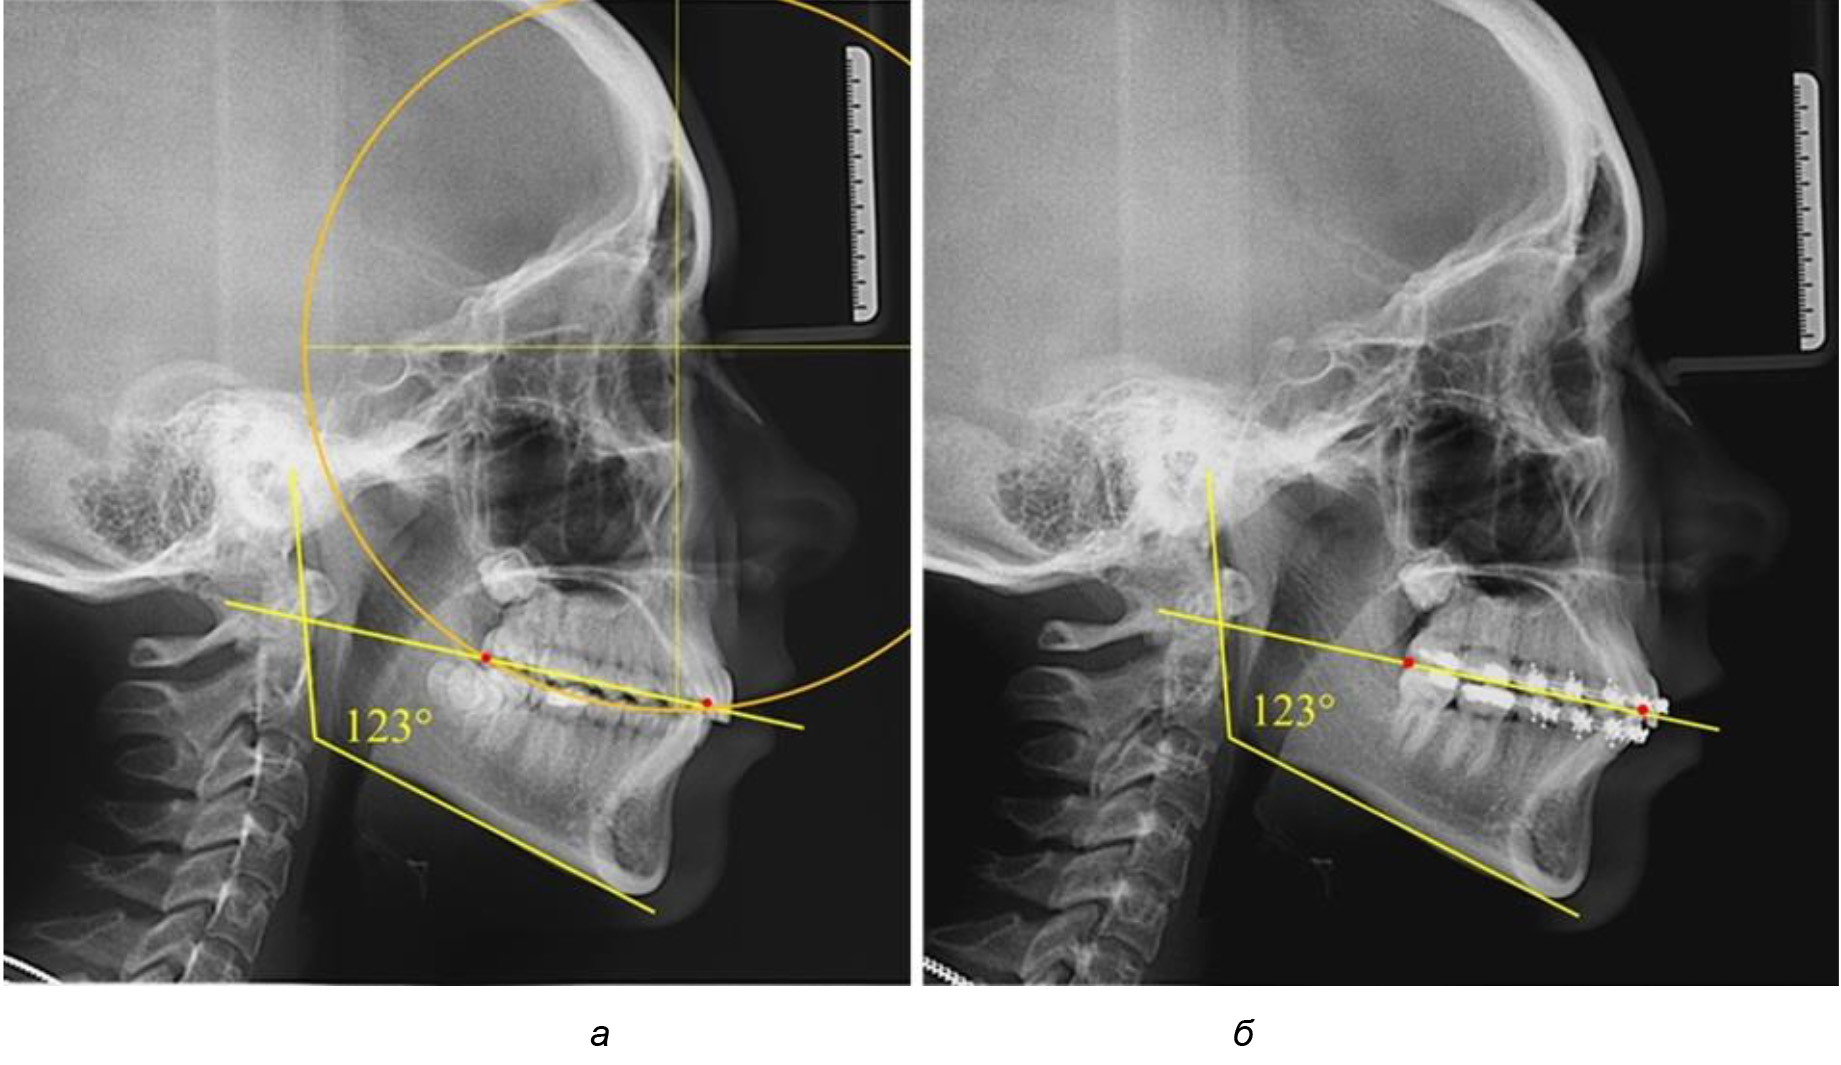

Рис. 1. Метод определения кривой Spee на ТРГ (а) и на ОПТГ (б)

При анализе латеральных ТРГ устанавливали реперный окклюзионные точки в переднем и боковом отделе. Передняя точка устанавливалась на режущем крае нижнего медиального резца, которую в клинике ортодонтии обозначают как vPOcP. Дистальная точка второго нижнего моляра обозначалась как hPOcP. Измеряли расстояние между окклюзионными точками, что определяло сагиттальный размер окклюзионной линии. Использование программ PowerPoint позволило проводить окружность, проходящую по линии смыкания зубов через окклюзионные точки. Измеряли радиус окружности. Учитывая вариабельность размеров окклюзионной линии и радиуса окружности, определяли относительный показатель через отношение радиуса круга к длине сагиттального размера окклюзионной линии. Глубину окклюзионной кривой измеряли от точки наибольшей выпуклости до окклюзионной линии (рис. 1). На ортопантомограмме (ОПТГ) также соединяли окклюзионные точки правой и левой стороны и измеряли глубину окклюзионной кривой от точки наибольшей выпуклости до окклюзионной прямой линии. Результаты глубины кривой Spee сравнивали по данным ТРГ и ОПТГ.

Деление величины радиуса круга к длине окклюзионной линии составило 1,623 ± 0,02. Таким образом, для определения радиуса окружности, соответствующей кривизне окклюзионного контура боковой ТРГ, необходимо измерить расстояние между передней и задней окклюзионными точками и последующим умножением полученной величины на число Фибоначчи (рис. 2).

Рис. 2. Особенности кривой Spee на ТРГ (а) и ОПТГ (б) у людей с признаками вертикального роста